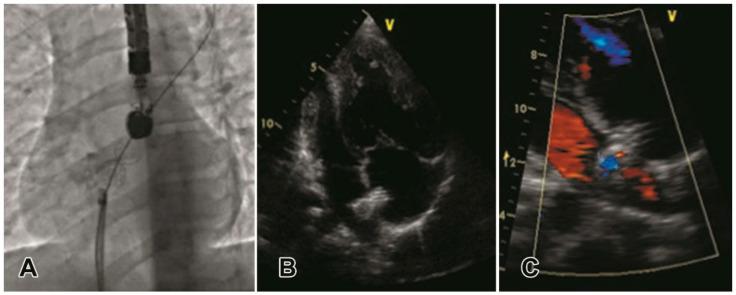

The aim of this study was to analyze results of stenting atrioseptostomy in patients with pulmonary arterial hypertension and a different level of risk for one-year mortality that is not well described. Patients that underwent atrioseptostomy with stenting were retrospectively divided in two groups: "intermediate" ( = 55) or "high" risk ( = 13), according to the 2015 ESC/ESR guideline. Results of atrioseptostomy were assessed during hospital period and at follow-up. Patients from "intermediate" risk group demonstrated lower mortality rate (10/55, vs. 6/13) during the course of the study period, as well as higher freedom from lung transplantation or Potts shunt. At discharge, patients of both groups presented improvement in functional class and mobility. Patients from "intermediate" risk group showed longer 6-min walking distance, and lower levels of brain natriuretic peptide. At the latest follow-up, stable position and full patency of stents with right-to-left or bidirectional shunt at atrial level and absence of syncope was confirmed in patients of both groups. Patients from the "intermediate" risk group demonstrated higher functional class, better performance of walking test, and lower levels of brain natriuretic peptide. Stenting atrioseptostomy reliably secured interatrial communication and improved clinical condition in patients with idiopathic pulmonary arterial hypertension. Mid-term results were better in "intermediate" risk group.